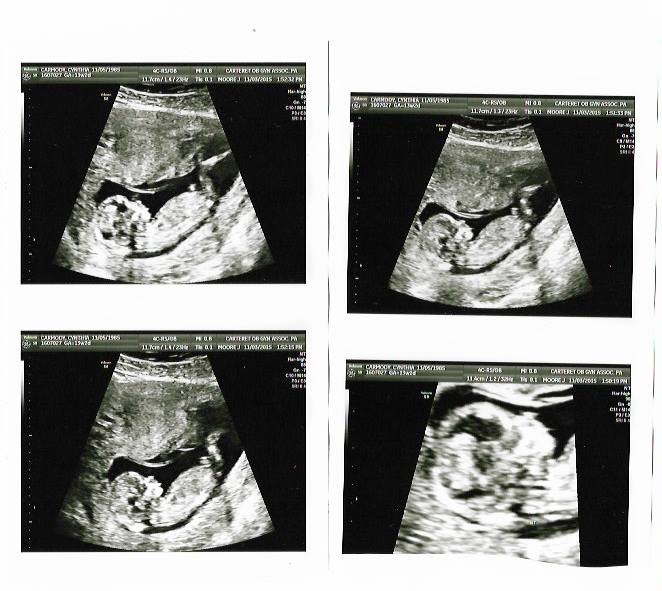

Attachment 28265Attachment 28261Attachment 28262Attachment 28263Attachment 28232Attachment 28232

I know I accidentally posted this in the wrong section. First time using this site, I didn't know how to delete it. But can you tell the gender with the pics posted?